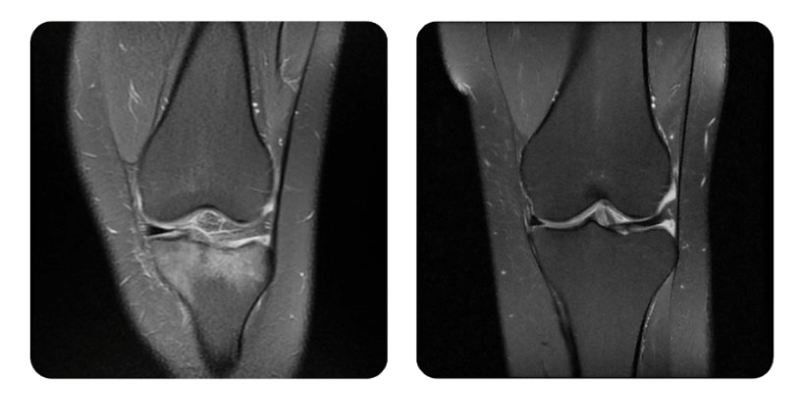

Prima

Dopo

T.C., 38 anni - Edema osseo a livello del piatto tibiale

Anamnesi: Paziente di 38 anni che si presenta per valutazione HBOT con anamnesi personale di edema osseo del piatto tibiale, con sottili linee di frattura a livello della porzione interna post-traumatica.

Risultati: RMN del ginocchio.

Evoluzione: Favorevole: la paziente riferisce un miglioramento del dolore gia dalle prime sedute, seguito da aumento della mobilita e guarigione completa confermata all'RMN.